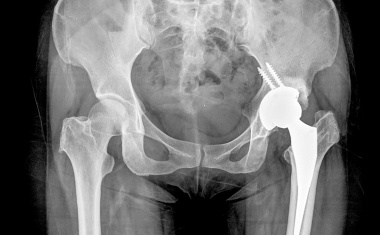

Hüft- und Knieprothesen: Welche Befestigung im Knochen ist die beste?

Ziel der Implantation eines künstlichen Hüft- und Kniegelenks ist die dauerhafte und stabile Verankerung der Prothese im Knochen. Nur so ist eine schmerzfreie Belastung des Kunstgelenks über idealerweise mehr als 20 Jahre möglich.